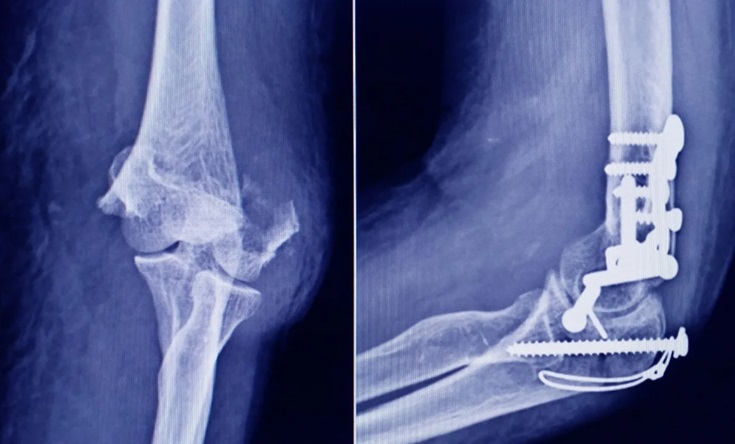

TORNILLOS EN CIRUGÍAS Crédito: Agencia NA (redes)

La Administración Nacional de Medicamentos, Alimentos y Tecnología Médica (ANMAT) advirtió a la población por un tornillo utilizado en cirugías traumatológicas debido a que es falso, por lo que su uso representa riesgo para la salud del paciente al que se lo implante.

Se trata de un tornillo utilizado en cirugías traumatológicas que fue detectado durante una inspección de control de mercado realizada en una ortopedia ubicada en la ciudad de San Miguel de Tucumán.